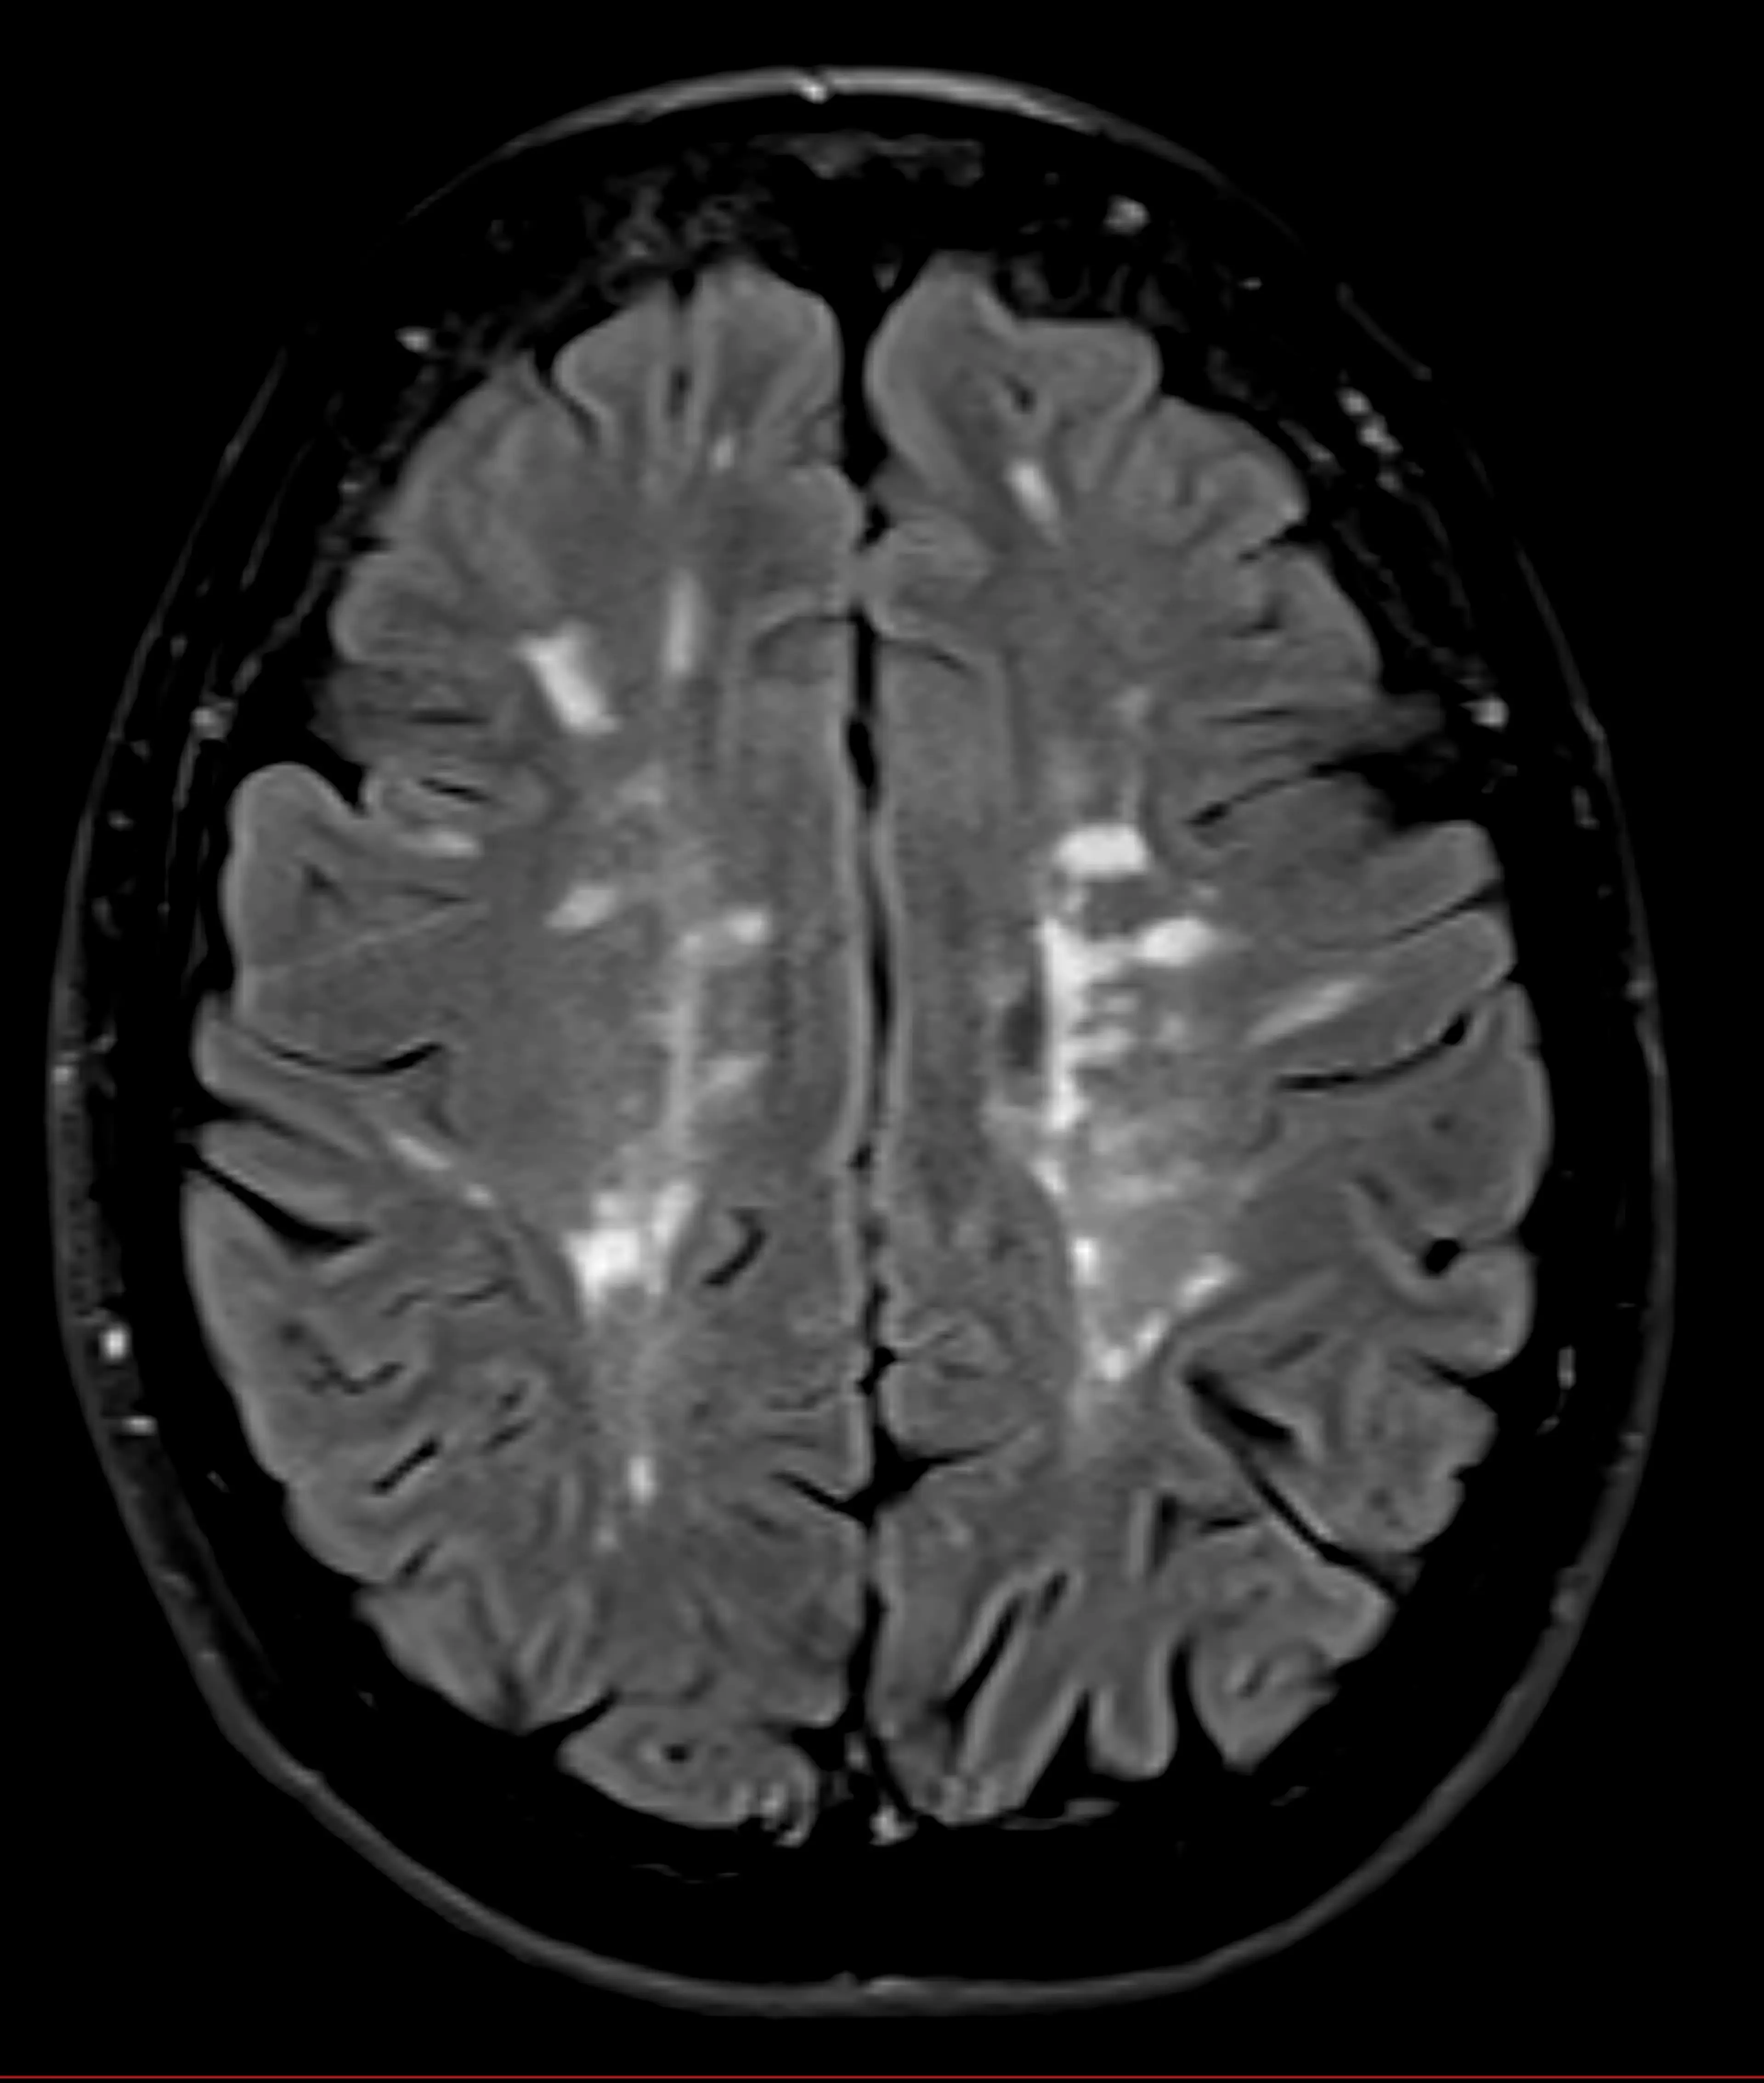

However, things like traumatic brain injuries, Wilson’s disease, and strokes have all been associated with episodes of uncontrollable laughter. The Multiple Sclerosis Association of America believes that MS lesions affect the areas of the brain which control emotions - causing the awkward behaviour.